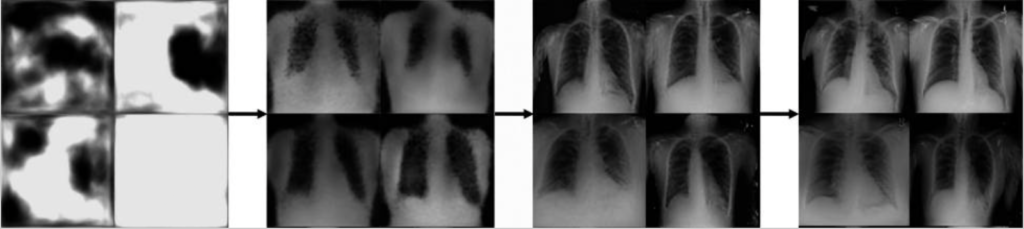

通过将机器学习的力量与医疗成像技术(如CT和MRI扫描)相结合,生成性人工智能算法可以加速医疗成像的精确性,并改善结果。

图9. 长达14小时的生成式人工智能模型的渐进式输出,产生了假的胸部X射线。(Source: Future Healthcare Journal)